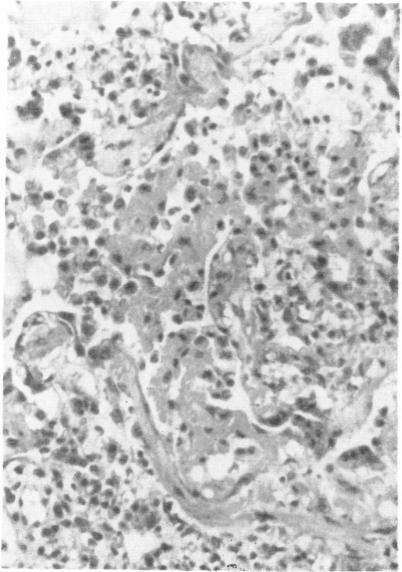

Antigens of Micropolyspora faeni were located by immunofluorescence in apparent association with alveolar macrophages within sections of lung from cases of bovine interstitial pneumonia. Pretreatment of frozen sections with pH 2.8 glycine-HC1 buffer was a necessary prerequisite for specific staining. Bovine immunoglobulin and bovine complement were identified in similar locations.

通过免疫荧光法在患牛间质性肺炎病例的肺切片中发现,微小多孢菌抗原明显与肺泡巨噬细胞相关。用pH 2.8甘氨酸 - 盐酸缓冲液预处理冰冻切片是特异性染色的必要前提。在相似位置鉴定出牛免疫球蛋白和牛补体。